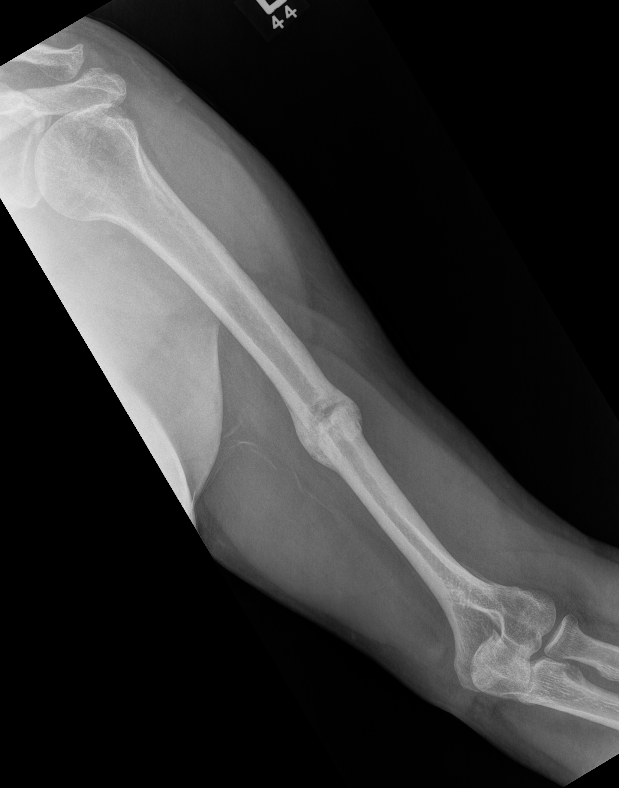

Humerus shaft 1Humerus shaft 3Humerus shaft 4Humerus shaft 5

Union of a midshaft humerus fracture treated nonoperatively

HumHumHumHum

Union of distal humerus fracture treated nonoperatively